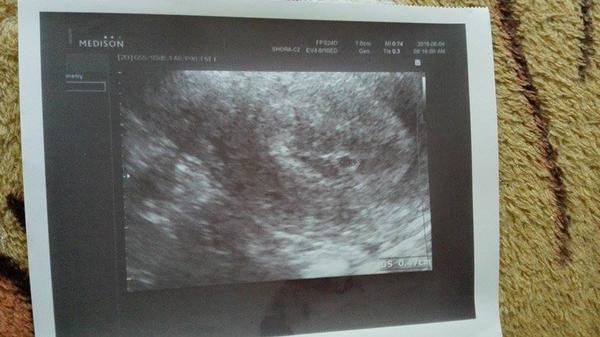

Děkuji 🙂 ale zatím nic v íc nevím ani v kolikátém týdnu sem asi to ještě nejde videt

@sukynecka01 moc moc gratuluju.....tak at krasne mimi roste ;) pěkná fotečka ;)

@adydejka2609 děkuji 🙂 jen se teším až mi řekne v kolikatem sem týdnu 🙂 protože sama nevím kdy ovuluji atd

@sukynecka01 v kolikatem jsi ti rekne max dle posledni MS....podle utz az tak v 7-8tt...takze si to vlastne muzes spocitat 🙂

Tak první foto :D